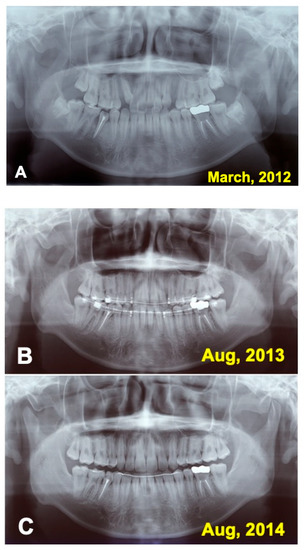

3.1. Gross View and Examinations after Surgery

3.2. Radiographic Evaluation